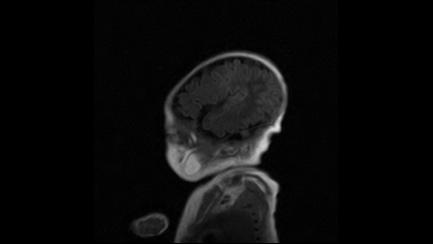

标题: PED3413:患儿女6天体检

缺血缺氧性脑病

6天为新生儿,髓鞘发育正常;左侧颞顶叶蛛网膜下腔增宽,请结合临床。

1。缺血缺氧性脑病2。左侧颞顶叶外部性脑积水,可观察

半卵圆中心上方层上可见对和乐大脑皮质t1高信号,考虑有hie可能,不知有何症状,建议加做dwi及复查

符合缺氧缺血性脑病影像表现。